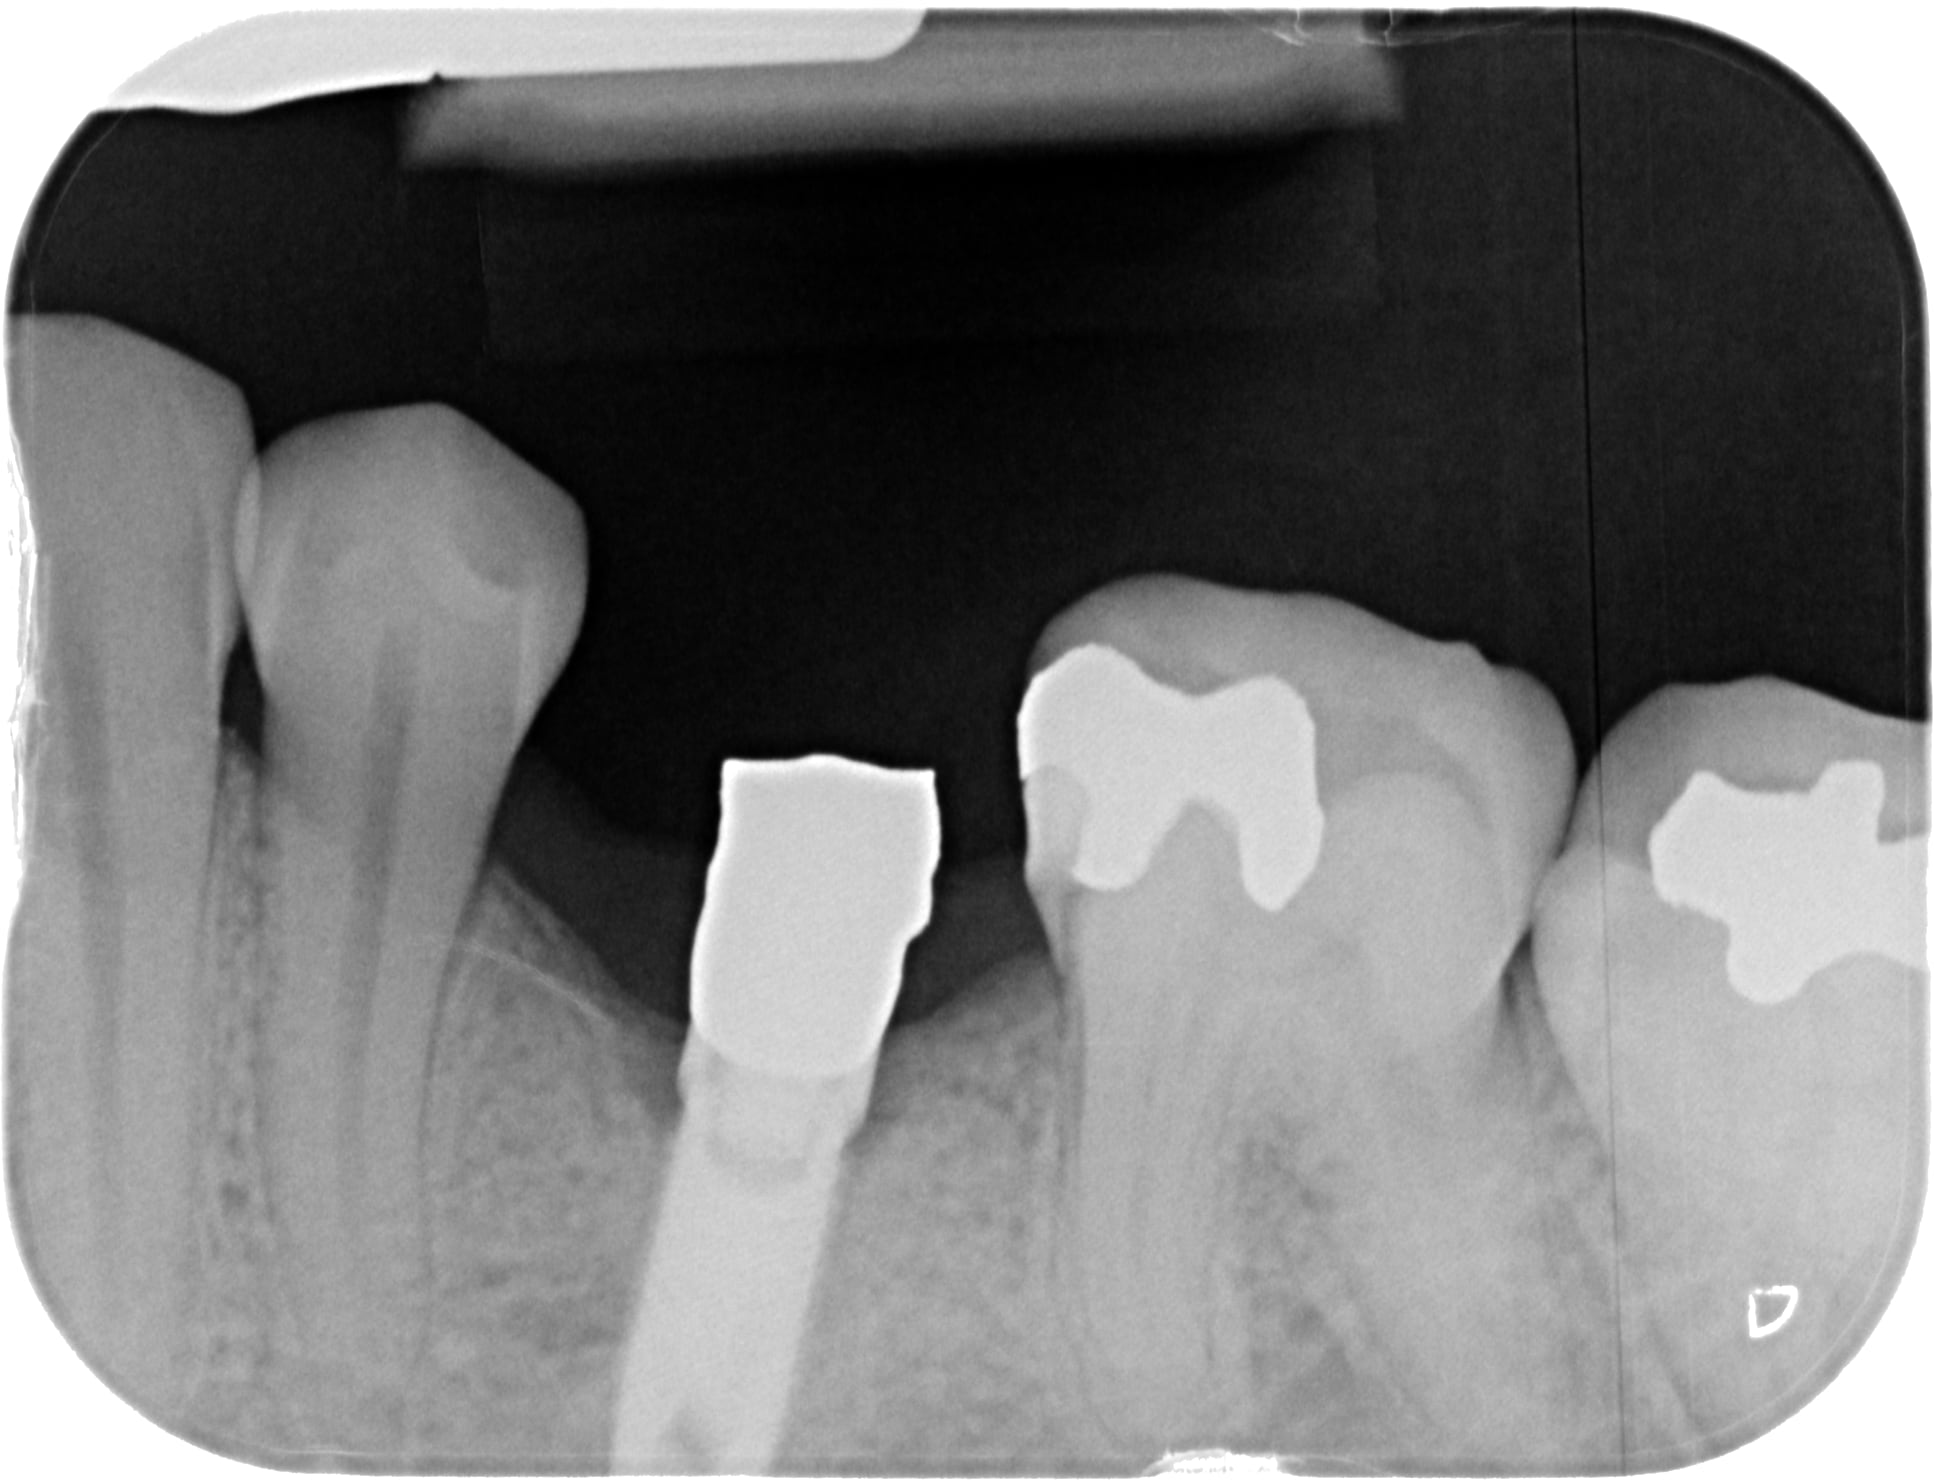

oui désolé... c'est mieux? plutôt Nobel la 35 non ?

les 2 autres photos (du même implant)....çà ressemble à du MIS Lance ou similaire....pour moi la connexion doit être un standard "Zimmer"....